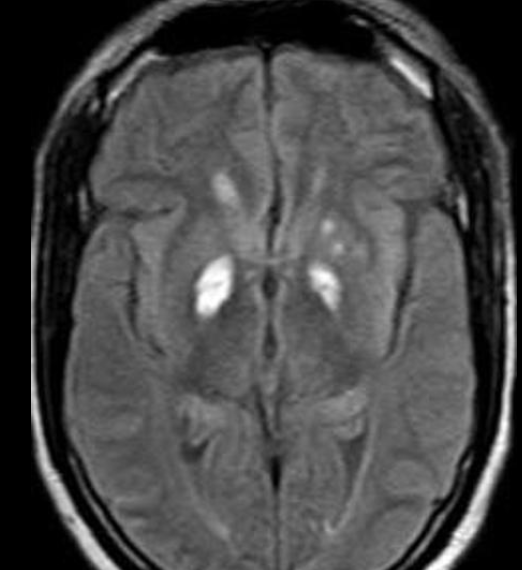

Imagem 4

5-fluorouracil (5-FU) e fludararabine